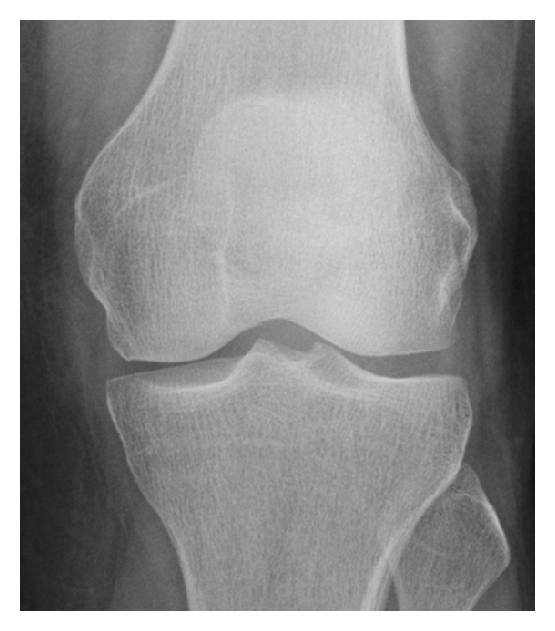

Fatigue fracture

Fatigue fracture 111 фотографий